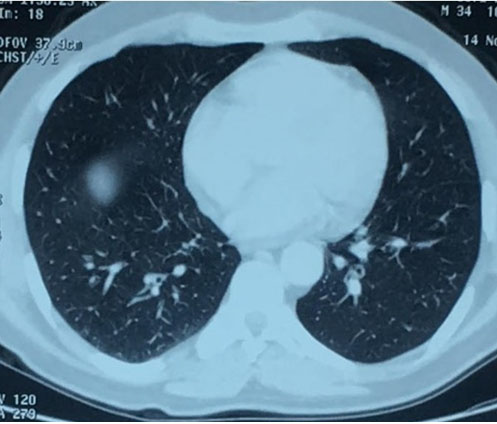

Complete blood count (CBC) showed hypereosinophilia to 7200 cells/mm3 with elevated erythrocyte sedimentation rate to 49 mm/h. Spirometry revealed obstructive syndrome. Electrocardiogram and transthoracic echocardiography were normal. Chest and paranasal sinus CT demonstrated ground-glass opacities (Figure 1) and severe pansinusitis (Figure 2). Skin biopsy showed necrotizing vasculitis with eosinophils (Figure 3) and ANCA were negative.

Figure 1: Chest computed tomography (CT) showed groundglass opacities.